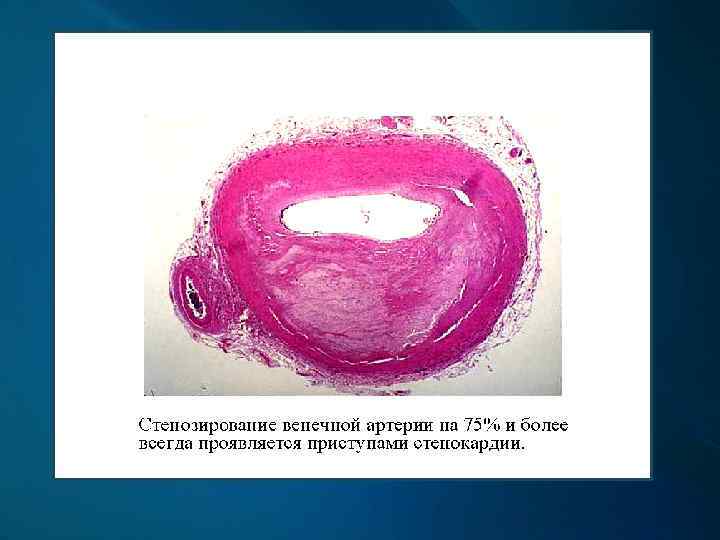

Клинические проявления и осложнения Атеросклероз венечных артерий сердца проявляется их стенозом, вызывающим приступы стенокардии, осложняется развитием инфаркта миокарда.

Венечная артерия на поперечном срезе с различной степенью атеросклеротического стеноза на разных участках